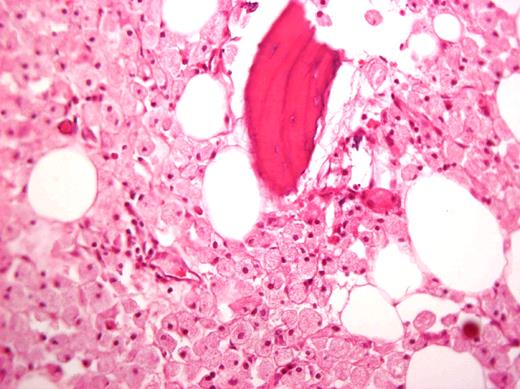

Magnetic resonance image of a 72-year-old man who did not respond to long-term high-dose ERT and improved after splenectomy. Courtesy of Dr George Blinder, Mar-Mor, Jerusalem, Israel.

Before commercially available ERT in the 1990s, management of patients with GD was largely symptomatic. Beyond blood transfusions, iron supplementation, and treatment of infections, the important therapeutic modality was surgery. Total or partial splenectomy was the mainstay for massive splenomegaly or severe pancytopenia, but it is less needed since the advent of ERT. However, even with ERT, there are patients with massive splenomegaly and devastating parenchymal damage, including focal lesions, fibrosis, or ischemia, which may limit the organ's ability to respond to ERT (Figure 2).40 We have performed total splenectomies in very few such patients who failed to improve despite years of ERT (including high-dose regimens), specifically, unchanged thrombocytopenia or splenic volume. Dramatic improvement after splenectomy has several features: immediate normalization of platelet counts; decreased fatigue and bleeding tendencies; amelioration of the mechanical component that induced early satiety, abdominal discomfort, and possibly exertional dyspnea; and, for young women, freeing the abdominal cavity for an expanding uterus during pregnancies. I therefore consider the option of splenectomy for patients with huge splenomegaly who are unresponsive to therapy. ERT should be continued after splenectomy to protect against skeletal damage and hepatic complications, although this cannot be guaranteed. Splenectomy today (even for huge organs) may be performed laparoscopically, with improved postoperative recovery,41 a procedure that has been performed successfully in 3 of our patients with massive splenomegaly.